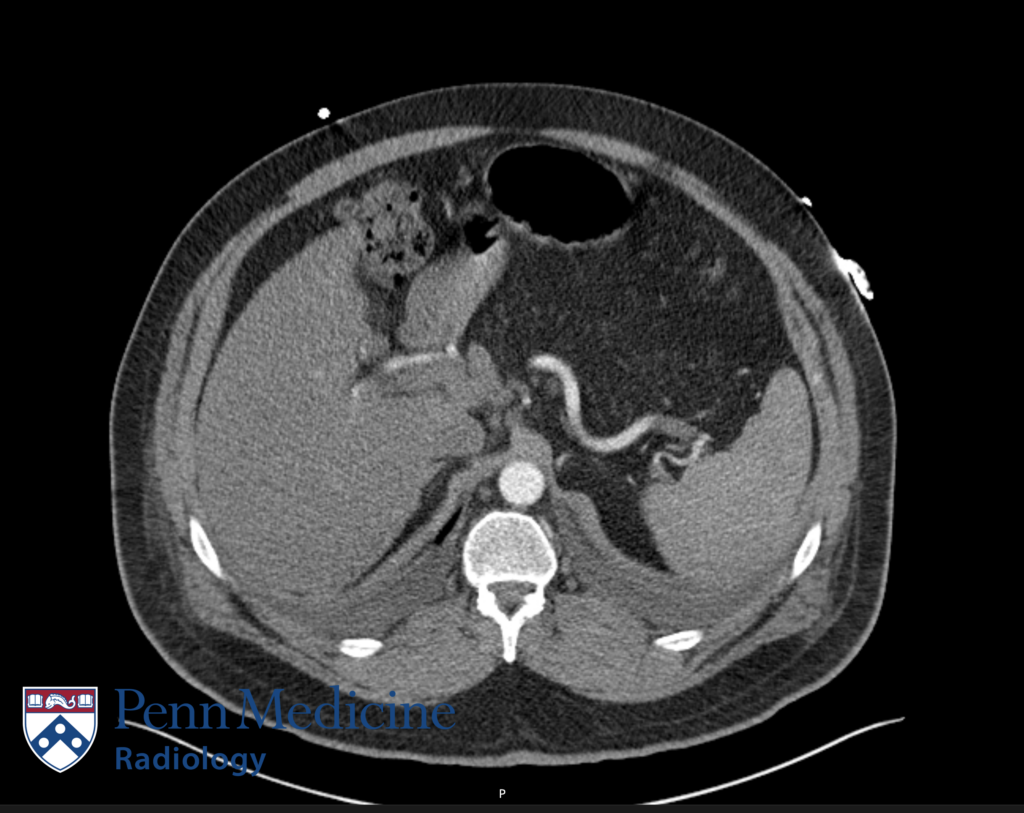

70-year-old woman undergoing follow-up imaging for pancreatic lesion

A 70-year-old woman undergoing follow-up imaging of a known pancreatic lesion.